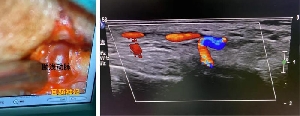

近期,神經(jīng)外一科疼痛功能團(tuán)隊(duì)在李永濤主任的帶領(lǐng)下,成功開展多例神經(jīng)血管減壓術(shù)治療偏頭痛,患者均得到治愈,擺脫多年頭痛頑疾困擾。病例1患者女,65歲,雙側(cè)顳部及枕部持續(xù)搏動(dòng)性跳痛30余年,就診我院頭面痛門診。郝懷勇主治醫(yī)師經(jīng)過細(xì)致的體格檢查,發(fā)現(xiàn)引起她頭痛的根源是顳部的耳顳神經(jīng)和枕部的枕大神經(jīng)。借助術(shù)中超聲